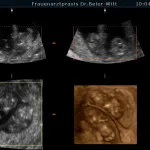

Besonders 4D-Ultraschall ist ein beeindruckendes Erlebnis, weil Sie Ihr Kind plastisch und in seinen Bewegungen sehen und auf Wunsch eine Videoaufzeichnung mit nach Hause nehmen können.

Der günstigste Zeitpunkt für diese Untersuchung ist zwischen der 26. und 32. Schwangerschaftswoche.

Wir müssen an dieser Stelle betonen, dass es sich nicht um eine notwendige medizinische Leistung handelt, und dass sie unsere sonstigen US-Untersuchungen nicht ersetzt.